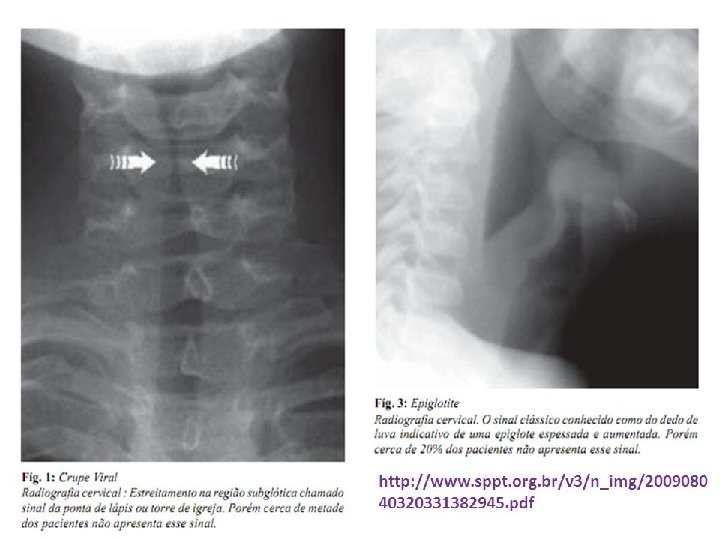

CRUPE viral Diagnóstico: ◦ Essencialmente clínico! ◦ Exame complementar: RX cervical: estreitamento da traquéia subglótica (Sinal da ponta de lápis ou sinal da torre)

Epiglotite Exame complementar: ◦ Hemograma: leucocitose >20. 000, com desvio para esquerda ◦ RX cervical lateral: Sinal do polegar